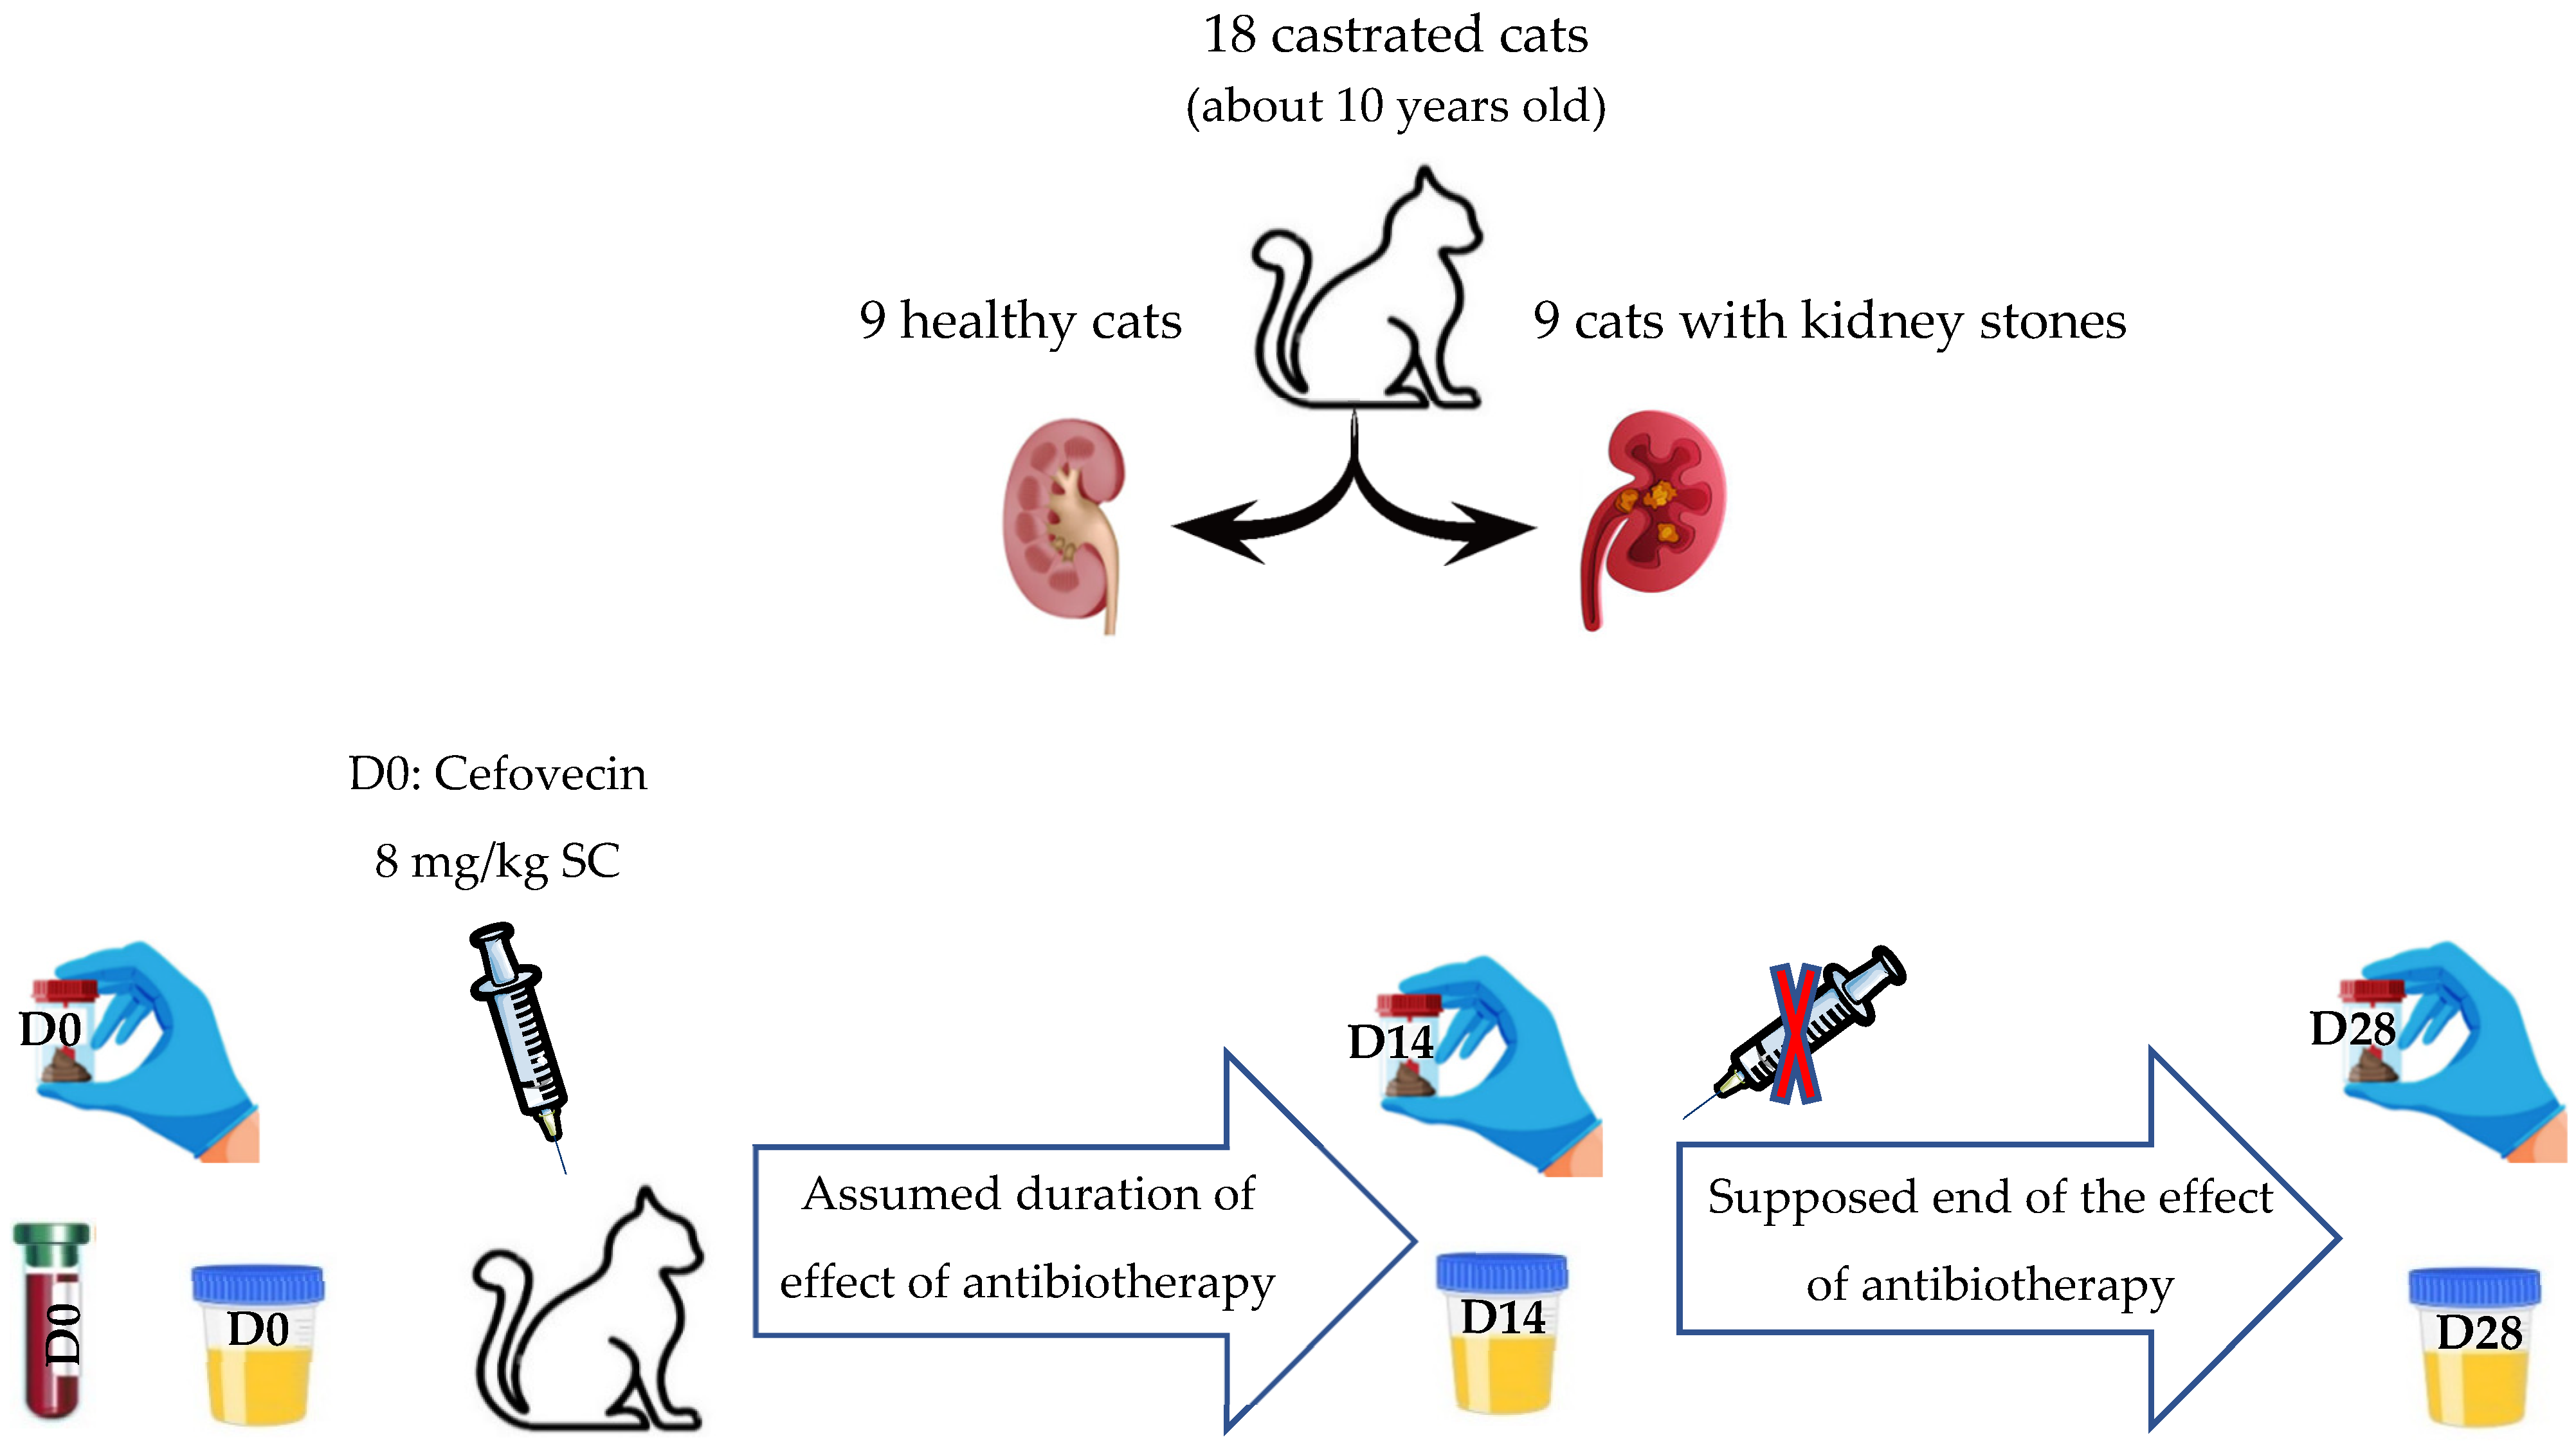

2. Materials and Methods

2.1. Studied Population

2.1.1. Recruitment of Cats

2.1.6. Follow-Up

2.2. Sample Collection

2.3. Antibiotic Therapy

2.4. DNA Isolation and 16S rRNA Amplicon Sequencing

2.4.1. High-Throughput Bacterial DNA Sequencing Techniques Used